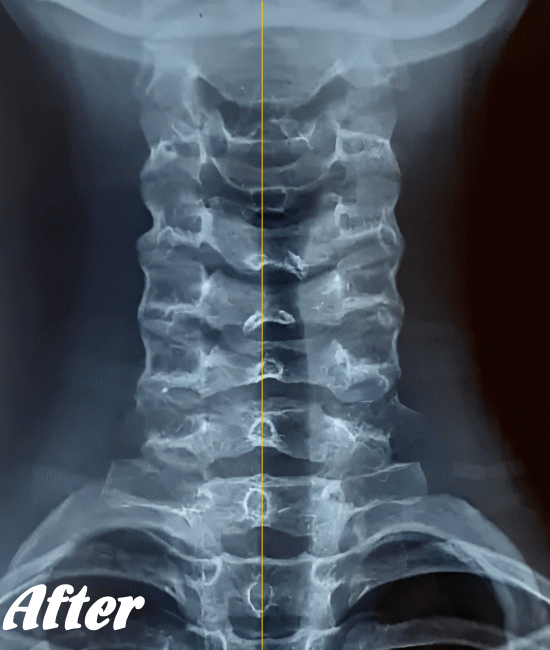

緊張型頭痛/肩こり頭痛の発生は、首背面の筋肉が緊張し血流が悪くなることが大きな原因だと考えられます。そこで、まずは首まわりや肩まわりの筋肉を緩め、潤滑な血行を確保させることを優先に施術します。

そのために、背骨の歪みを整え、肋骨、肩甲骨、首や首の付け根など、血流を阻害している部位の筋骨格をすべて調整します。